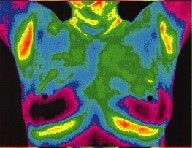

Why Breast Thermography?

Breast Thermography is an adjunctive diagnostic procedure approved by FDA for breast cancer screening.

Breast Thermography spots changes in a breast 8 to 10 years ahead of mammograms.

Breast Thermography delivers no radiation to the breast.

Breast Thermography requires no compression nor any contact with the breast to create images.